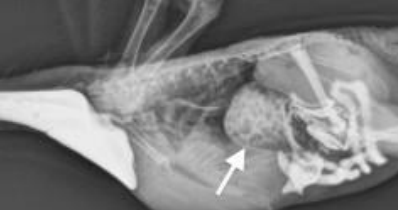

PPD/Bornavirus is diagnosed by an enlarged which organ on radiography? Fluoroscopy, GI biopsies, RT-PCR on crop swab, serology, and post-mortem exam are also used.